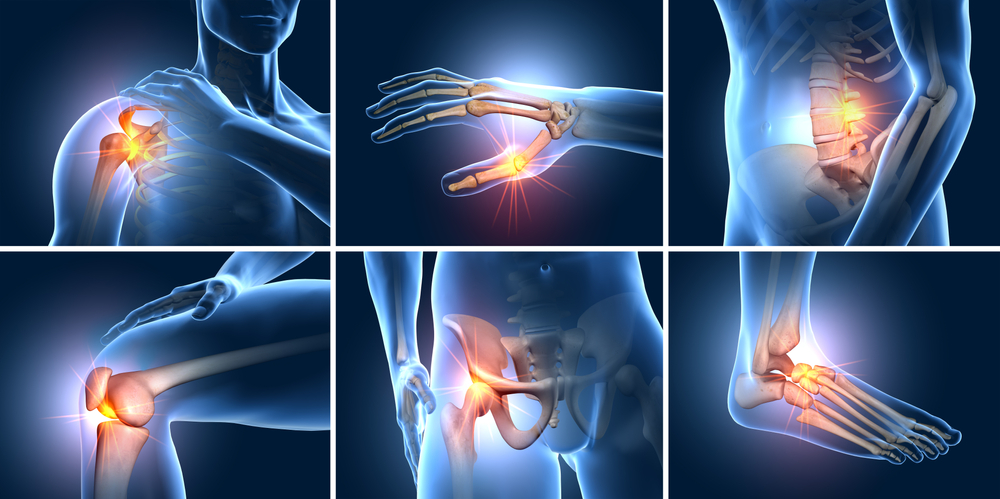

Physiotherapy Treatments

Joint Pain

Frozen Shoulder